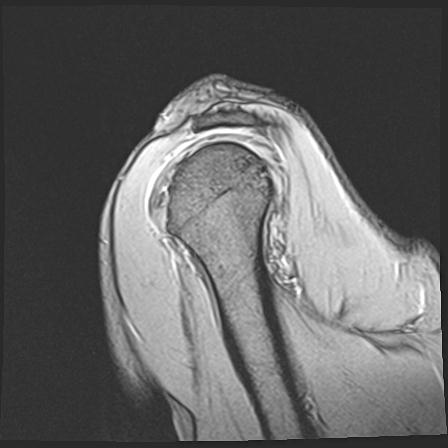

60058 3/9 11/4 右肩 2R+MRI 73歳男性 肩腱板損傷